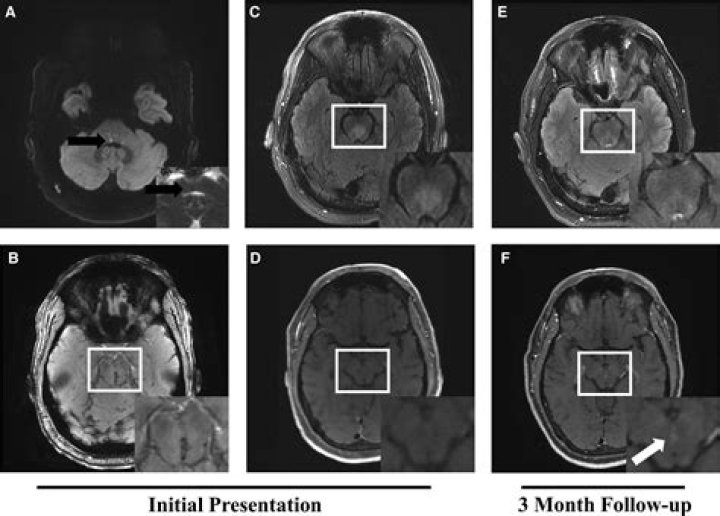

What does a venous angioma look like?

16-9). The angiographic appearance of venous angiomas is multiple, dilated medullary veins appearing in the venous phase and converging toward a central, equally dilated, draining vein with a caput medusae appearance.